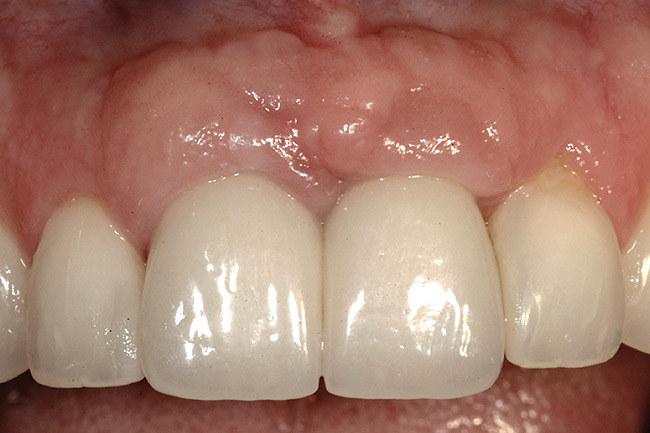

Figure 9  The final restorations exhibit a minimal 1-mm to 1.5-mm change in papilla height when compared with the pre-extraction height.

Figure 9